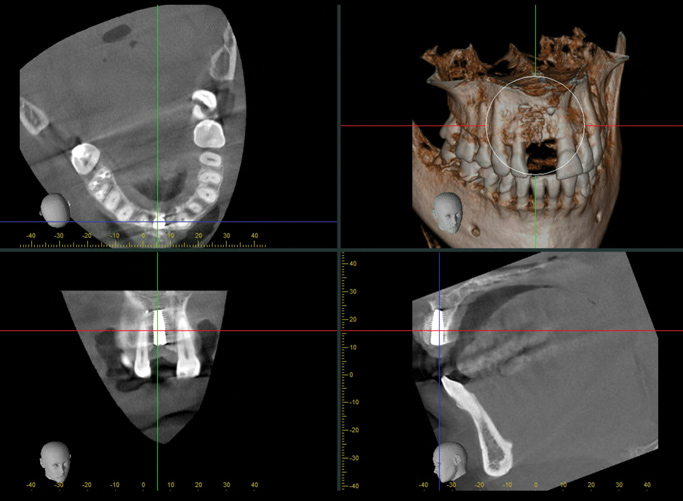

(7.) Pretreatment CBCT scan.

Figure 7

A 56-year-old female patient was referred for the evaluation of tooth No. 8 (Figure 4 and Figure 5). A periapical radiograph indicated that the tooth had undergone apicoectomy and received an excessively long post (Figure 6), and a cone-beam computed tomography (CBCT) scan of the site revealed a lack of buccal plate bone (Figure 7).

When the patient returned 4 months after the initial procedure for reevaluation, she underwent supportive periodontal therapy and was provided with detailed oral hygiene instructions (Figure 13). An intraoral scan and a postoperative CBCT scan were taken to evaluate both the horizontal and vertical hard- and soft-tissue gain. Next, implant planning software was used to merge the STL and DICOM data, which facilitated the creation of a digital wax-up (Figure 14).

The digital wax up allowed the implant position to be planned based on the ideal prosthetic position of the final restoration (Figure 14). The planned implant position adhered to the aforementioned guidelines for ideal implant placement regarding the buccal, interproximal, and apical bone, and its platform would be located 4-mm apical to the planned restorative margin. In the coronal plane, the implant was centered with the gingival zenith in a position that was located approximately 1-mm distal to the midline of the edentulous space. Following implant planning, a tooth-supported surgical guide was designed and then 3D-printed to facilitate fully guided surgical implant placement.